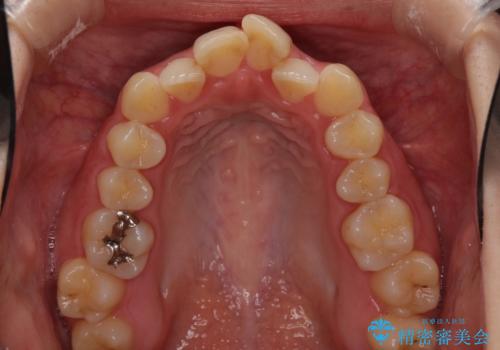

前歯のクロスバイトを治したい インビザラインによる矯正治療

- 前歯のデコボコとクロスバイトを治したいとのことで来院された患者様です。

上下顎ともに歯列全体の側方拡大とIPR(歯と歯の間を削る)によってデコボコとクロスバイトが解消するように設計し、インビザラインにより治療を行うこととしました。

下顎骨の左側への骨格的なずれが強く、上下の正中の位置合わせや奥歯の咬み合わせ構築に苦労しました。